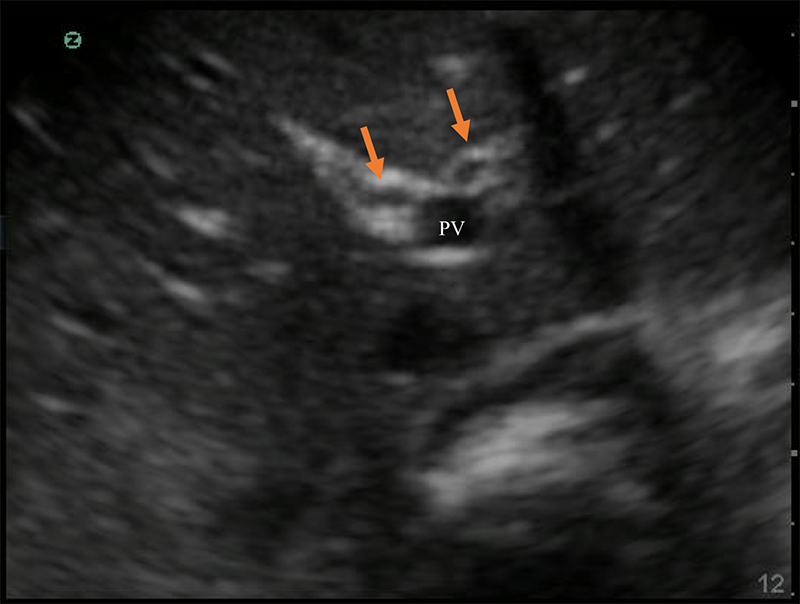

Figure 10. The portal triad seen in short axis. The portal vein (PV) is the largest, while the hepatic artery and bile duct (arrows) are much smaller and often indistinguishable without color Doppler.